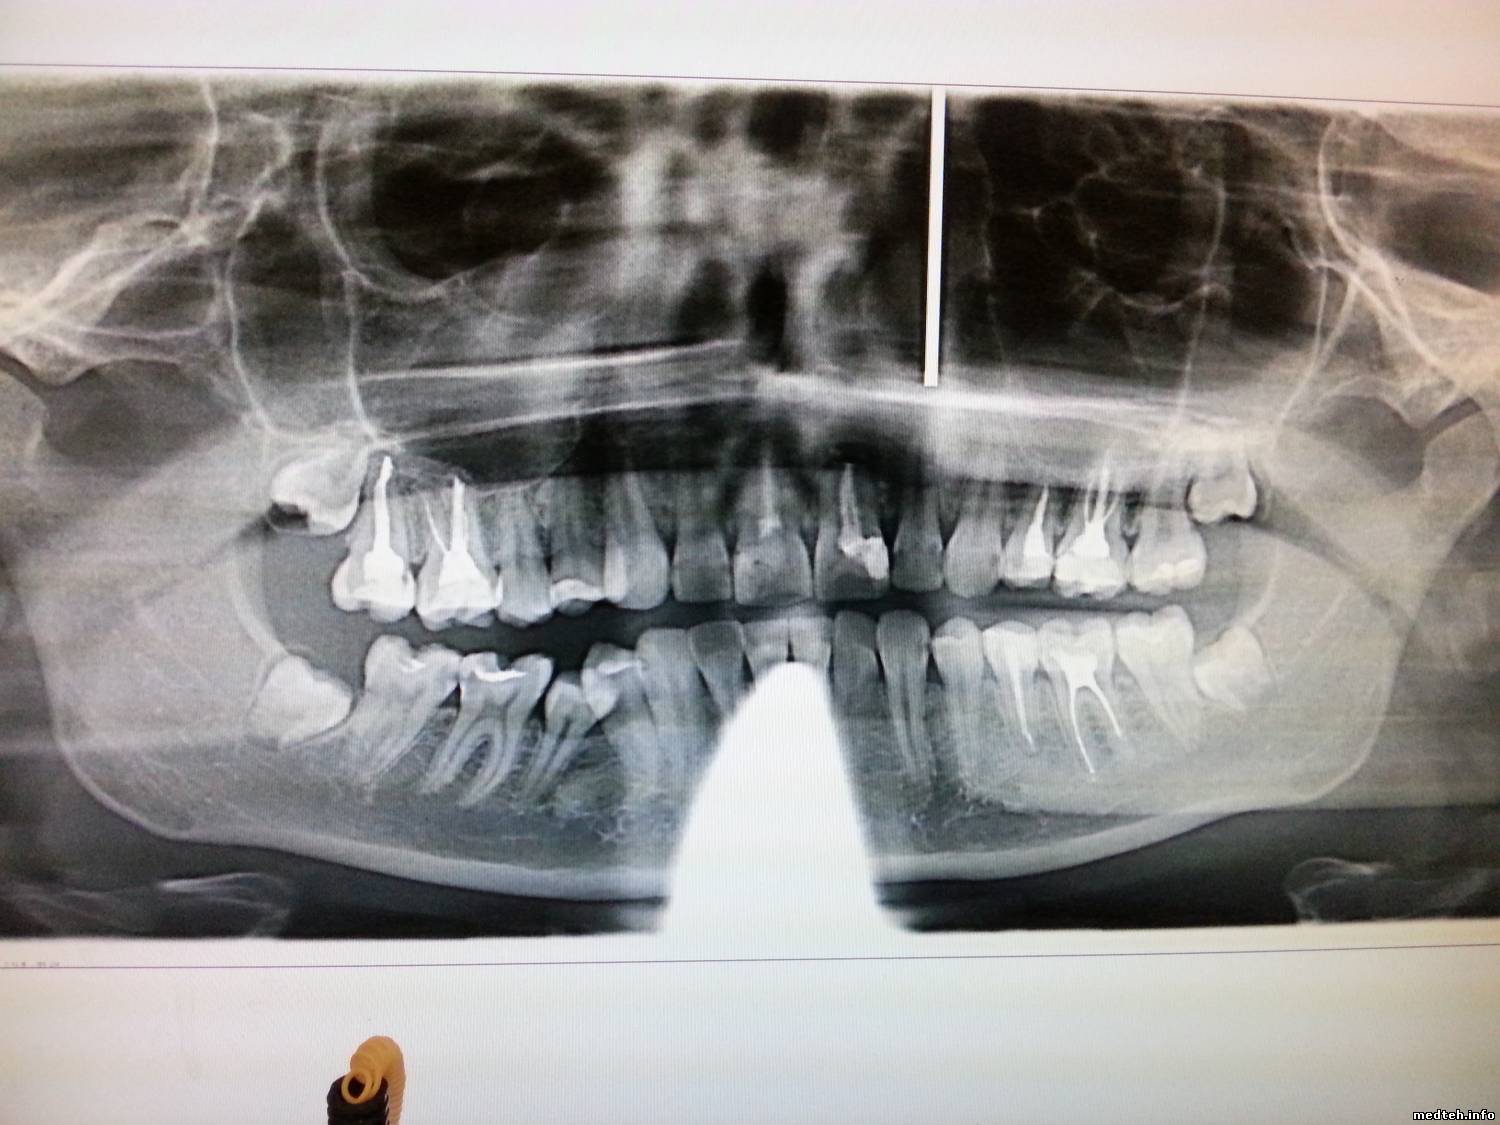

Стали возникать вырывы в верхней трети изображения (периодически), также присутствуют моменты расфокусировки и пропадания изображения в середине нижней части снимка.

4430131.jpg (159.4 Kb) · 2981457.jpg (153.2 Kb) · 8950514.jpg (149.7 Kb)

Нижняя часть снимка: - передник с воротником + неправильное позиционирование(второй снимок).

Передник тут ни причём. "Воротник" появляется периодически без всякой системы, таких снимков за год набралось около сотни.

Похоже после ухода за ширму рентгенлаборанта пациент расслабляется и втягивает голову (снимки №1 и 3).

Датчик болтается (болезнь Sirona) + неправильное позиционирование.

МастерБаку предложил дельную мысль, попробую обязательно, но также беспокоит дефект верхней части снимка ireful $IMAGE3$$IMAGE1$$IMAGE2$ Это к вопросу о модели аппарата. Всем.

Неровные края сверху и снизу - это огрехи сборки. Даже думаю, что на заводе.